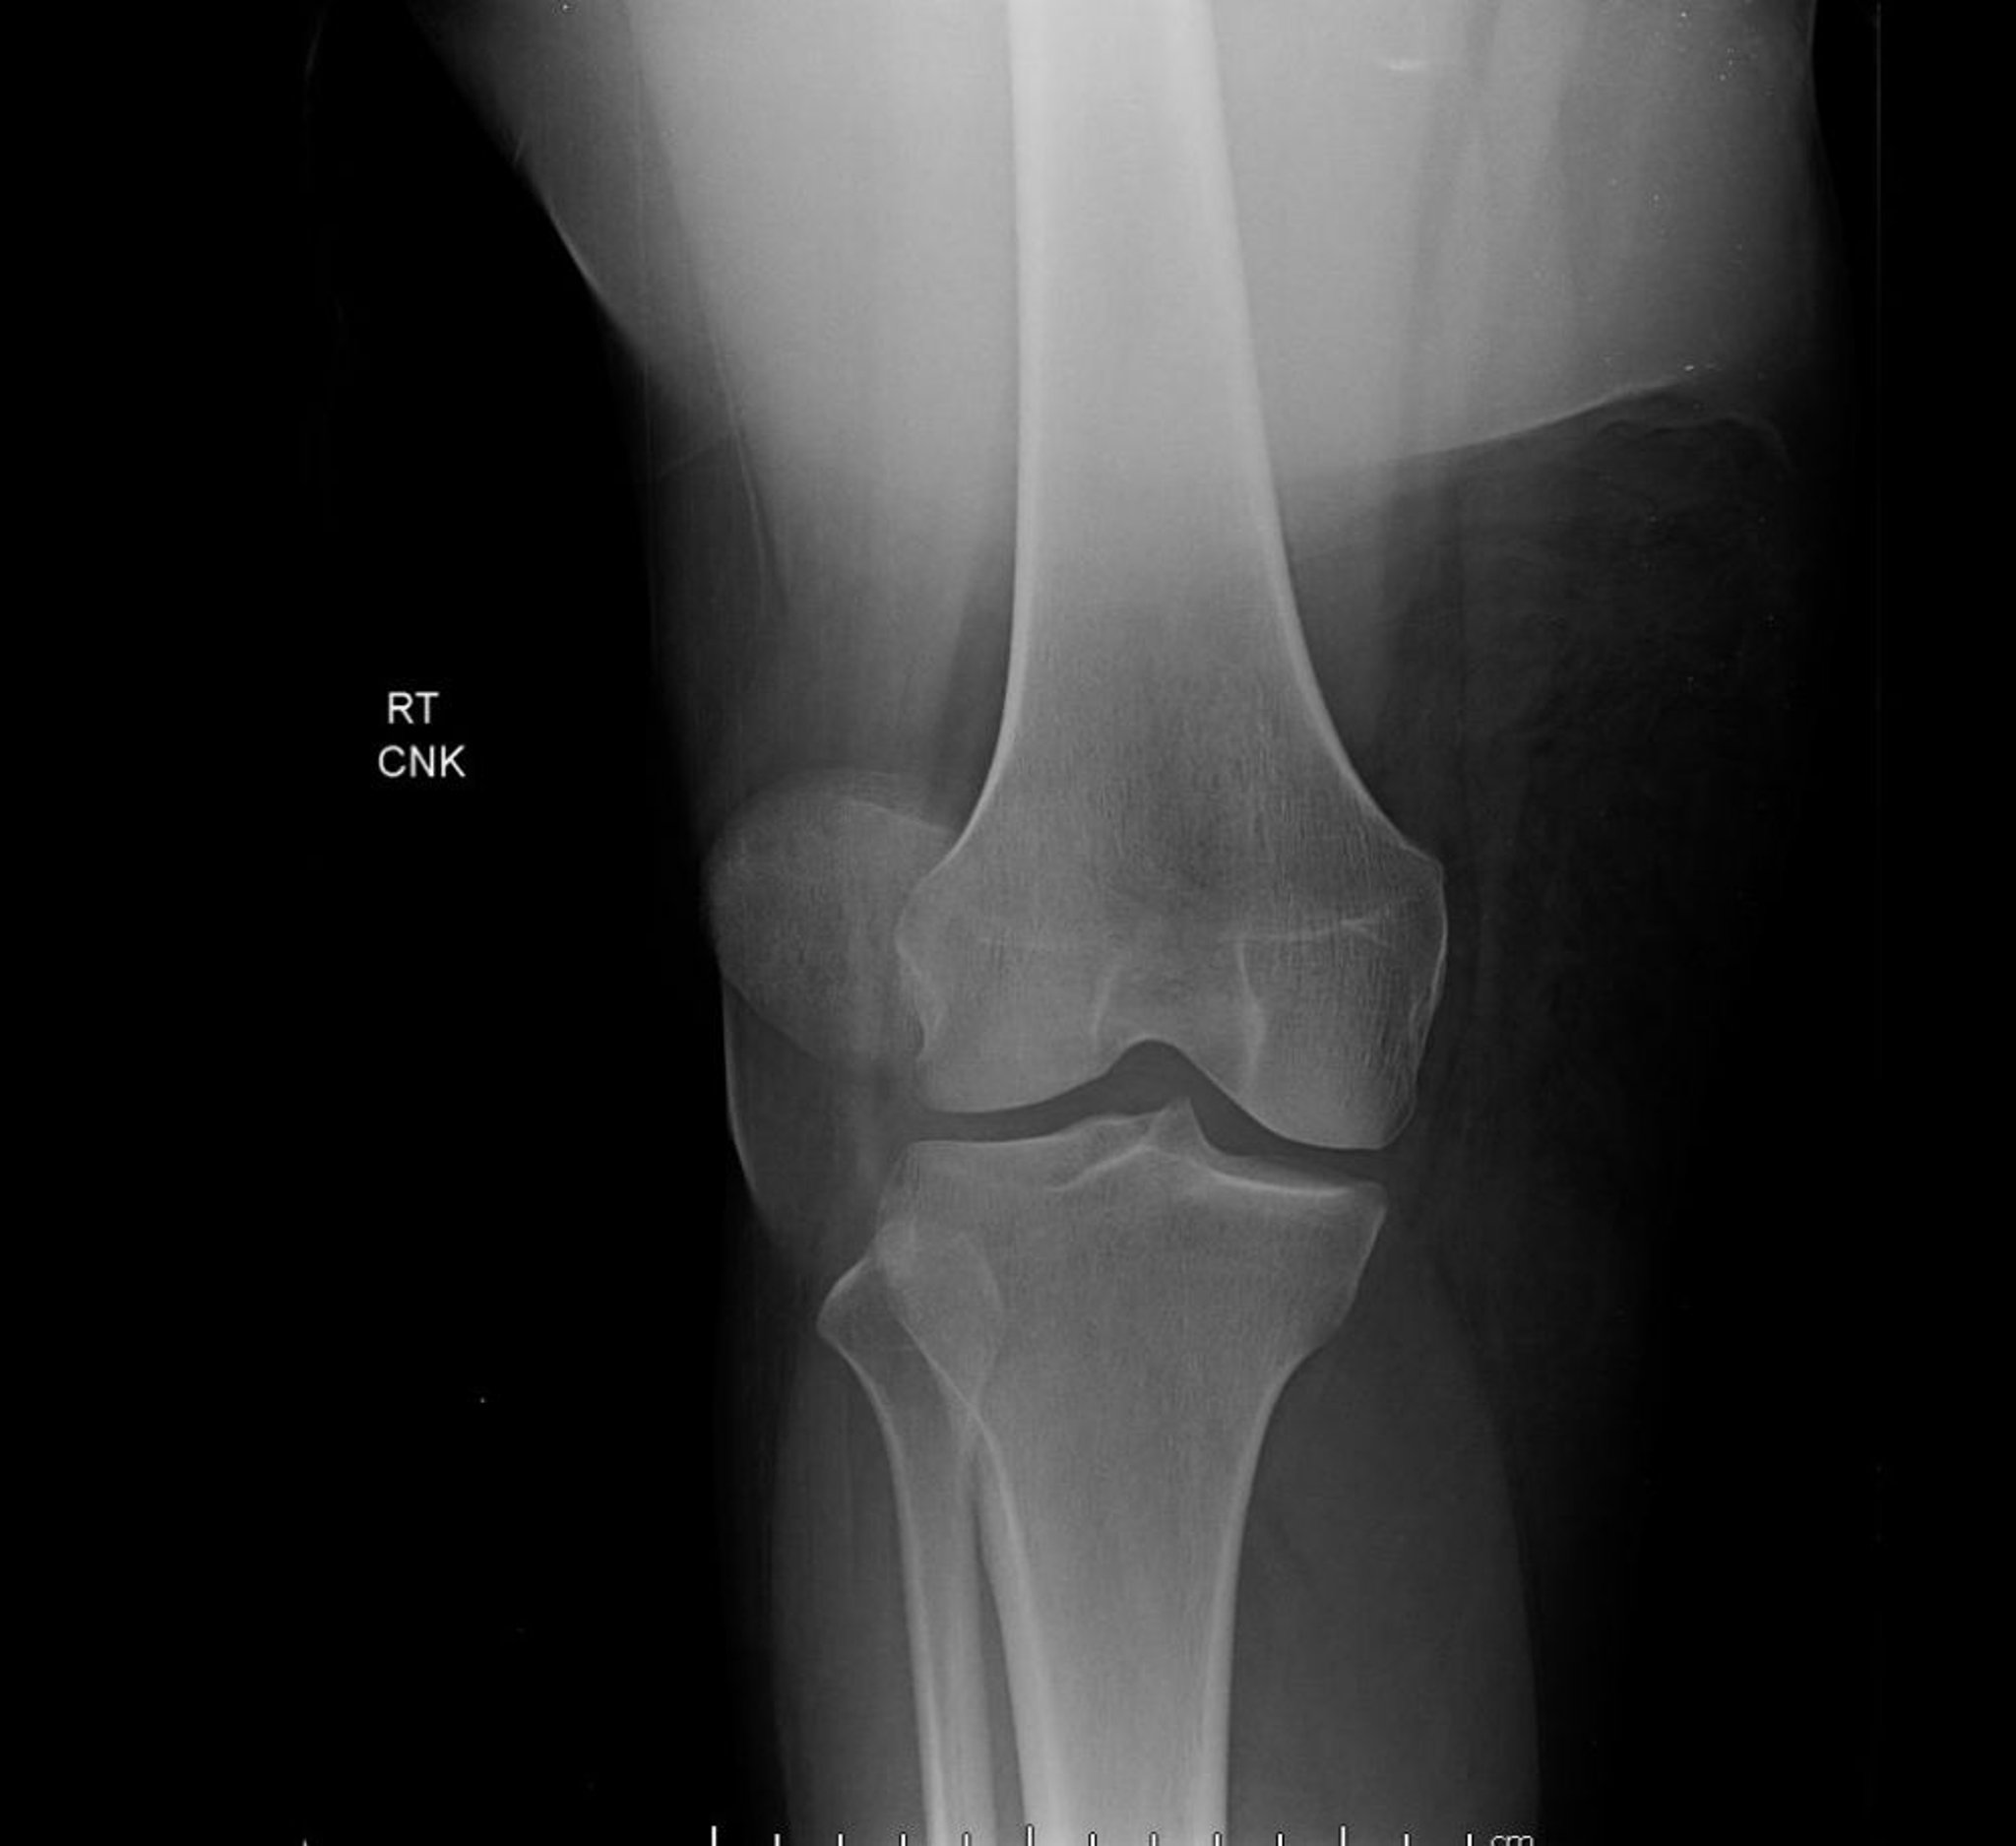

Luxación de la rótula (radiografía)

Esta vista anteroposterior de la rodilla muestra una luxación rotuliana, caracterizada por un desplazamiento lateral extremo de la rótula, fuera de su ubicación normal entre los cóndilos femorales.

Image courtesy of Danielle Campagne, MD.